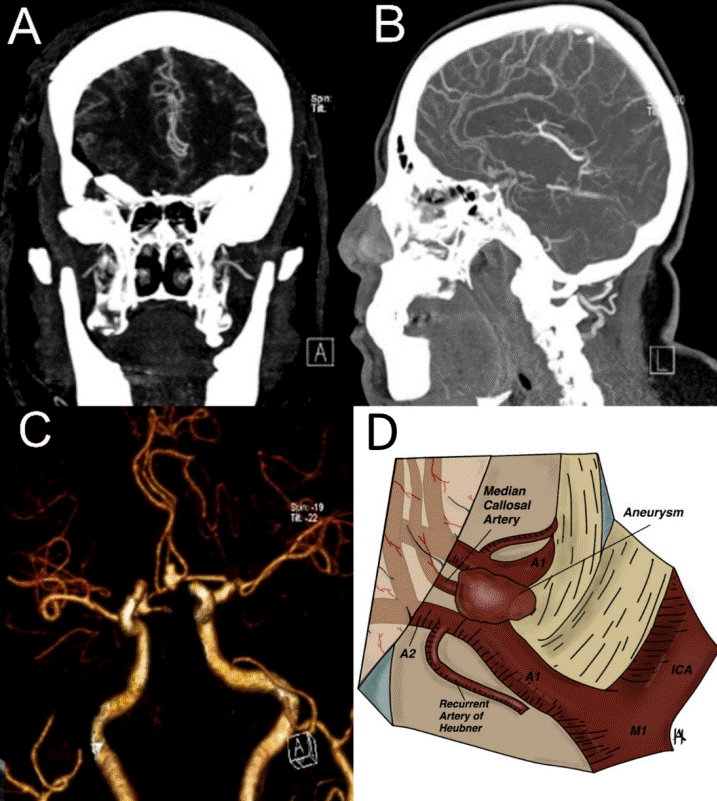

A 59-year-old woman with a previous history of smoking and alcohol consumption, poorly controlled chronic arterial hypertension, and associated obesity, with a body mass index (BMI) of 40 kg/m2, arrived at the emergency room due to cephalalgic syndrome with secondary characteristics consisting of frontotemporal bilateral intense severity associated with loss of consciousness and posterior recovery. The patient presented transient motor aphasia with full recovery after one hour. Physical examination revealed morbid obesity with no other findings. Neurologic examination showed meningeal signs with a positive jolt accentuation maneuver and nuchal rigidity. Simple computerized tomography (CT) scan showed a subarachnoid hemorrhage and a left Sylvian clot corresponding to Fisher I, Hunt-Hess II, and World Federation of Neurological Surgeons (WFNS) I. CT angiography revealed a superior projecting anterior communicating aneurysm and a median callosal artery (Figure 1).

Figure 1 Preoperative aneurism. A, B. Preoperative CT angiography in coronal and sagittal projections with evidence of an AComA aneurysm with a superior projecting dome and a median callosal artery. C. 3D reconstruction showing the vascular preoperative relations of the aneurysmal dome. D. Anatomy diagram of the anterior communicating complex with the aneurysm. CT: computerized tomography; AComA: anterior communicating artery; 3D: three-dimensional; A1: precommunicating segment; A2: infracallosal segment; Ml: sphenoidal segment; ICA: internal carotid artery.